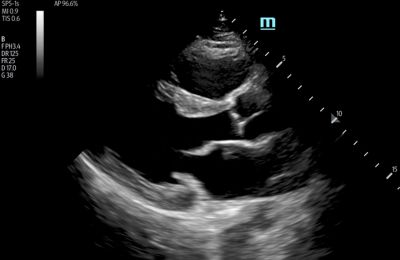

1. High-Resolution Images

Image quality and image-enhancing feature sets are typically top of mind when looking for a new ultrasound machine. The quality of the image directly impacts patient care, so it is important that you select a system that provides the quality you need to arrive at the appropriate diagnoses.

When evaluating a machine, pay careful attention to image resolution. For instance, ensure the machine offers excellent contrast resolution — its ability to distinguish between tissues with different levels of brightness. A high-quality ultrasound machine will show the subtle differences between tissues to enable a precise diagnosis.

Also, consider software features that enhance image clarity and reduce unwanted artifacts — images that don't represent real anatomical structures. This includes image processing algorithms like speckle reduction and spatial compounding, which reduce noise and improve image quality.